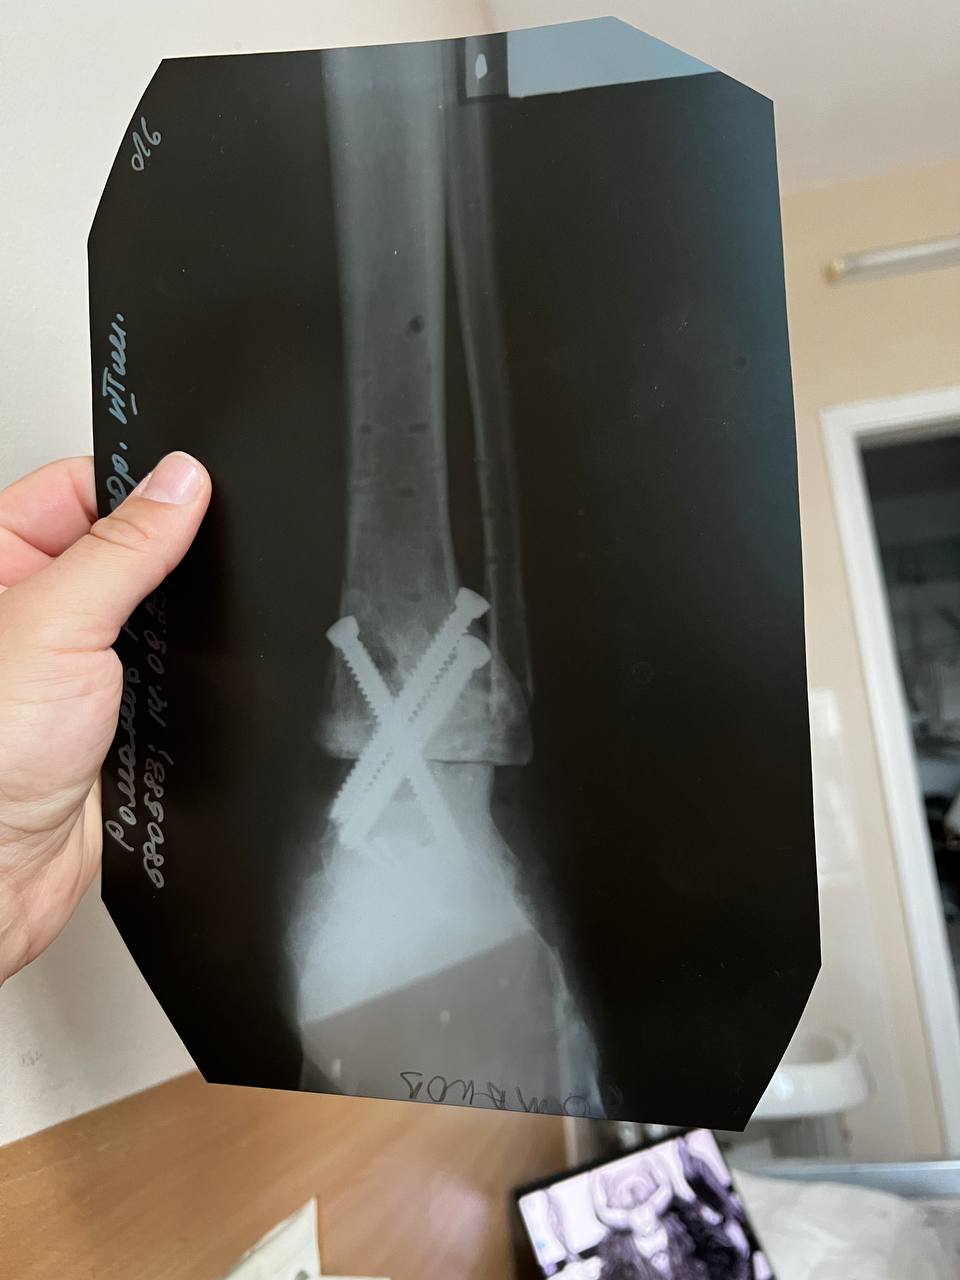

У Руслана був закритий перелом лівої ноги - кінцівка була зламана нижче коліна до кінчиків пальців. Йому за більш ніж рік провели чотири операції, і зараз замість суглоба три великих гвинти. Також після травми довелося з обох сторін зашивати щелепу.

"Відновлення триває й зараз, вже більше року. Через півроку після поранення почав ставати на ноги. Три місяці я взагалі майже не ставав - організм був практично на нулі, крутилося в голові, не міг спати. Плюс - цілий рік у мене були дуже сильні болі, бо зросталися кістки. Було дуже важко психологічно і фізично. Особливо перші три місяці були дуже важкі. Зрештою почав ходити на двох милицях, потім з однією милицею. Намагався ходити без милиці, але не виходило. І зараз можу пройти лише невелику відстань сам", - ділиться чоловік.